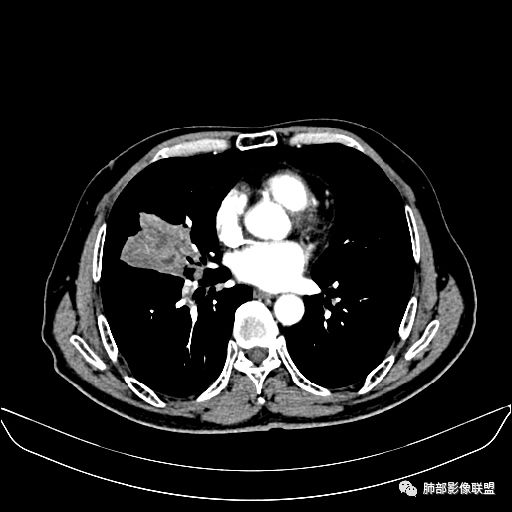

住院4天后行胸部增强CT

静脉期

老年男性,因“咳嗽咳痰1月余。”入院。病程中咳嗽咳痰,咳黄白痰,间断咯少许鲜红色痰血。PPD阳性。胸CT:右肺中叶外侧段支气管管腔阻塞,大片实性病变,病灶边缘光滑,部分边缘膨隆,可见分叶,肺门及纵隔可见肿大淋巴结,并可见钙化。增强可见病灶明显强化,而且延迟强化明显,病灶内多发低密度区,内见血管影,血管变细、部分血管破坏。考虑恶性病变可能性大,鉴别慢性肉芽肿性病变。

胸CT:跨叶大肿块,主体在中叶,右中叶外侧段支气管阻塞,病灶部分边缘膨隆,可见分叶,部分边缘平直,肺门及纵隔可见肿大淋巴结。增强病灶不均匀强化,延迟强化明显,病灶内多发低密度区,内见血管飘浮,部分血管变细、模糊。考虑:恶性病变可能性大,大细胞?淋巴瘤?鉴别慢性肉芽肿性病变。

右肺中叶软组织肿块,外围向内生长,叶间胸膜向前内移位,肿块近肺门侧跨叶,中叶外侧段支气管截断,密度不均匀,双侧肺门及隆突下见肿大淋巴结,增强后呈中度不均质强化,肺动脉供血,多发坏死区,边界尚清,坏死区域内见结构,结合病史考虑恶性,鉴别诊断1结核,爬行征是沿支气管树分布,外宽,内窄,周围有卫星灶,内气管狭窄后扩张,此例沿叶间胸膜长轴分布,气管有截断,不典型。2炎性肉芽肿,符合的地方下方层面增强后延迟性轻度环形强化,不符临床无发热等急性感染病史,实验室指标不符,病灶周围渗出及慢性炎性改变有,不明显。

吴婧老师和南边老师都对该病例进行了深入分析。从支气管管壁的增厚,支气管狭窄后扩张,支气管粘液栓,病灶形态,到病灶不均匀强化及坏死彻底,到周边病灶及肺组织空气的潴留,加之纵隔内淋巴结肿大伴钙化等等,都支持慢性炎性病灶,尤其是结核。

墨西哥仙人掌征---结核        影像上结核灶,粗大的均匀枝干,推测是支气管囊状扩张引起的,在非支气管区,形成圆形坏死囊群;如果这些坏死比较稀薄,又遇到扩张支气管,就会形成粗大的“墨西哥仙人掌”。结核引起的支气管近端炎症纤维化,可以造成支气管阻塞,从而将干酪样坏死物封堵在管腔内。仙人掌主干内部应该是干酪为主,稀薄的,具有流动性,时间久了会出现钙化。

结核坏死与鳞癌鉴别有一点是结核坏死没有方向性,鳞癌有。鳞癌靠近支气管近端部分,血供容易维持,不易坏死,所以坏死靠外侧。而结核干酪样坏死,把一定体积的流动性坏死物,包裹起来,什么形状最省料?坏死物包裹,表面积最省的自然是圆球形,而遇到支气管,坏死物一多,就把支气管撑大了。包裹物是就地取材,扩张的支气管就成了包裹结构。